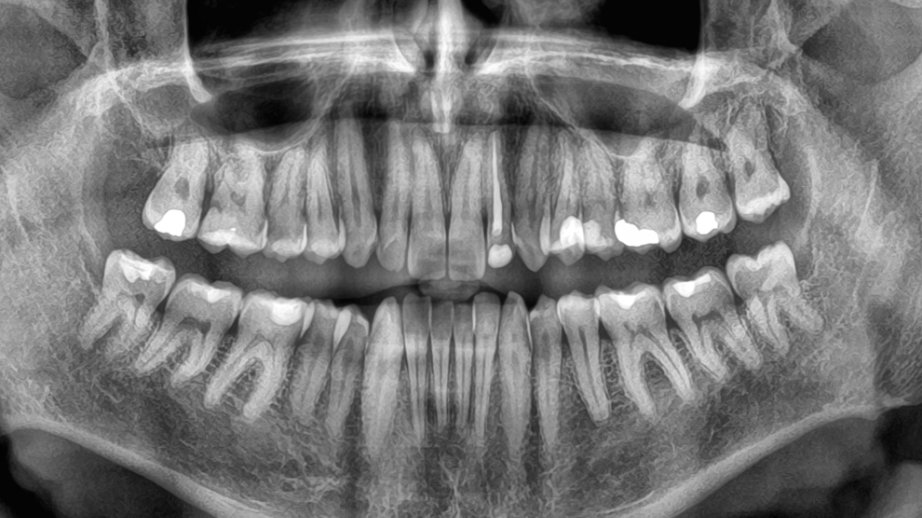

Araşdırma: Diş itkisi ölüm riskini artıra bilər

Yeni bir araşdırma göstərib ki, yaşlı insanlarda dişlərin sürətlə itirilməsi ölüm riskinin artması ilə əlaqəlidir. Çinli alimlər 3,5 il ərzində 8073 yaşlı insanı izləyərək belə nəticəyə gəliblər.

AZƏRTAC “sciencealert.com” portalına istinadla xəbər verir ki, tədqiqatın nəticələrinə görə, dişlərin itirilmə sürəti nə qədər yüksəkdirsə, bütün səbəblərdən ölüm riski də bir o qədər artır. Bu əlaqə yaş, cins, təhsil, içki və məşq vərdişləri kimi digər amillər nəzərə alındıqdan sonra da qalır. Mütəxəssislər bildirirlər ki, dişlərin itirilməsi birbaşa ölümə səbəb olmur, lakin diş itkisinə yol açan sağlamlıq problemləri, məsələn, iltihab, pis qidalanma və ürək xəstəlikləri ömrü qısalda bilər. Alimlər diş itkisinin insanın ümumi sağlamlıq vəziyyətini qiymətləndirmək üçün göstərici kimi istifadə oluna biləcəyini vurğulayırlar. Həkimlər dişlərin qorunması üçün müntəzəm diş həkimi müayinəsini, gündə iki dəfə fırçalamağı və siqaretdən uzaq durmağı tövsiyə edirlər.